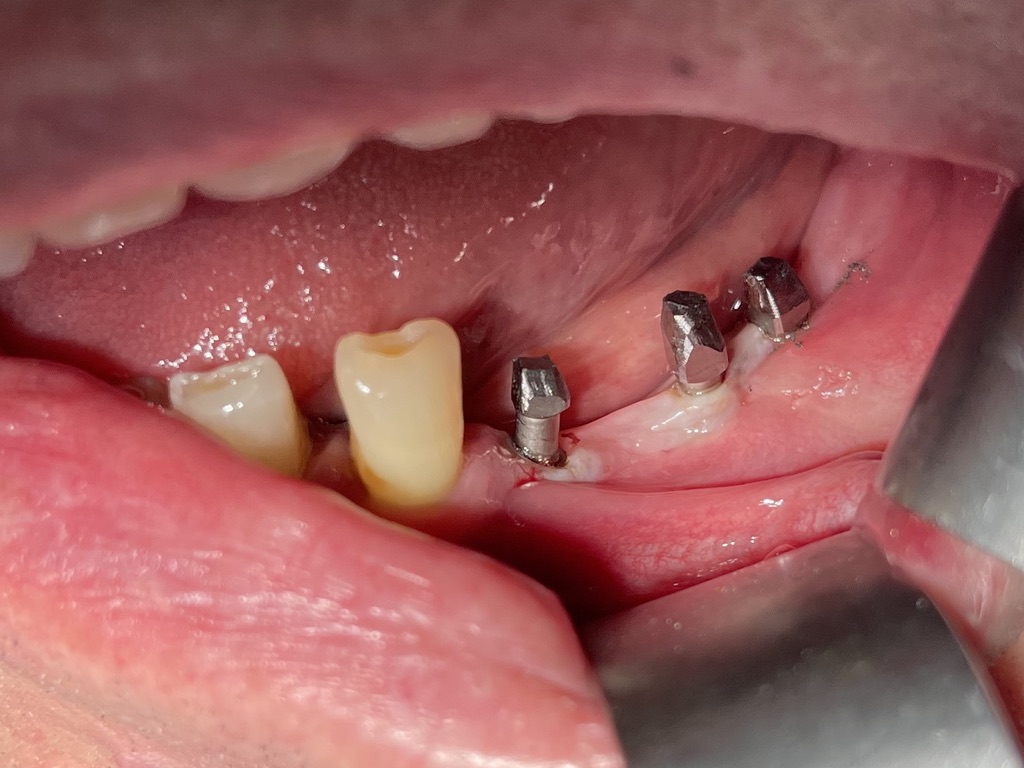

4 - TRAMONTE IMPLANT IN ADVANCED AGE

A patient with Tramonte implants for 28 years needs more implants, but is now almost 90 years old and takes a lot of medicines.